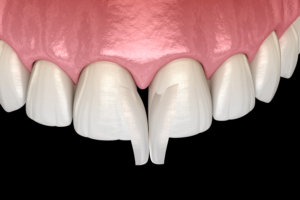

Günümüzde diş estetiği popüler hale gelmiştir. Bu amaçla yapılan uygulamaların bu üç amacı da yerine getirmesi mühimdir. Bu sebeple estetik amaçlı yapılan protezlerden önce mutlaka minimal invaziv(minimum müdahalecilik) yaklaşımların uygulanması gerekmektedir.

Zira bütün tıbbi uygulamalarda artık minimal invaziv yaklaşımlar ön plana çıkmaktadir. Bu sebeple dişlere sabit protez uygulamaları yapmadan önce diğer daha basit uygulamalar denenmelidir. Bunların hem geri dönüşü vardır hem de daha kolay ve ucuzdurlar. Bunlara örnek olarak gülüş tasarımında minik dişeti operasyonları, dişlerin renkli ve lekeli olmaları durumunda dolgu restorasyonları ve/veya diş ağartma uygulamaları kullanılanabilir. Bunlara hekiminizle ortak bir şekilde karar verebilirsiniz.